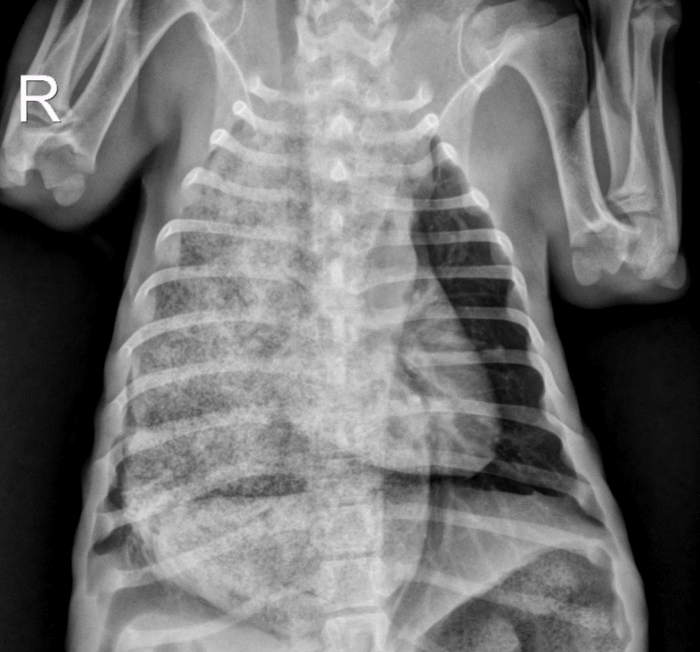

Juvenile idiopathic megaesophagus